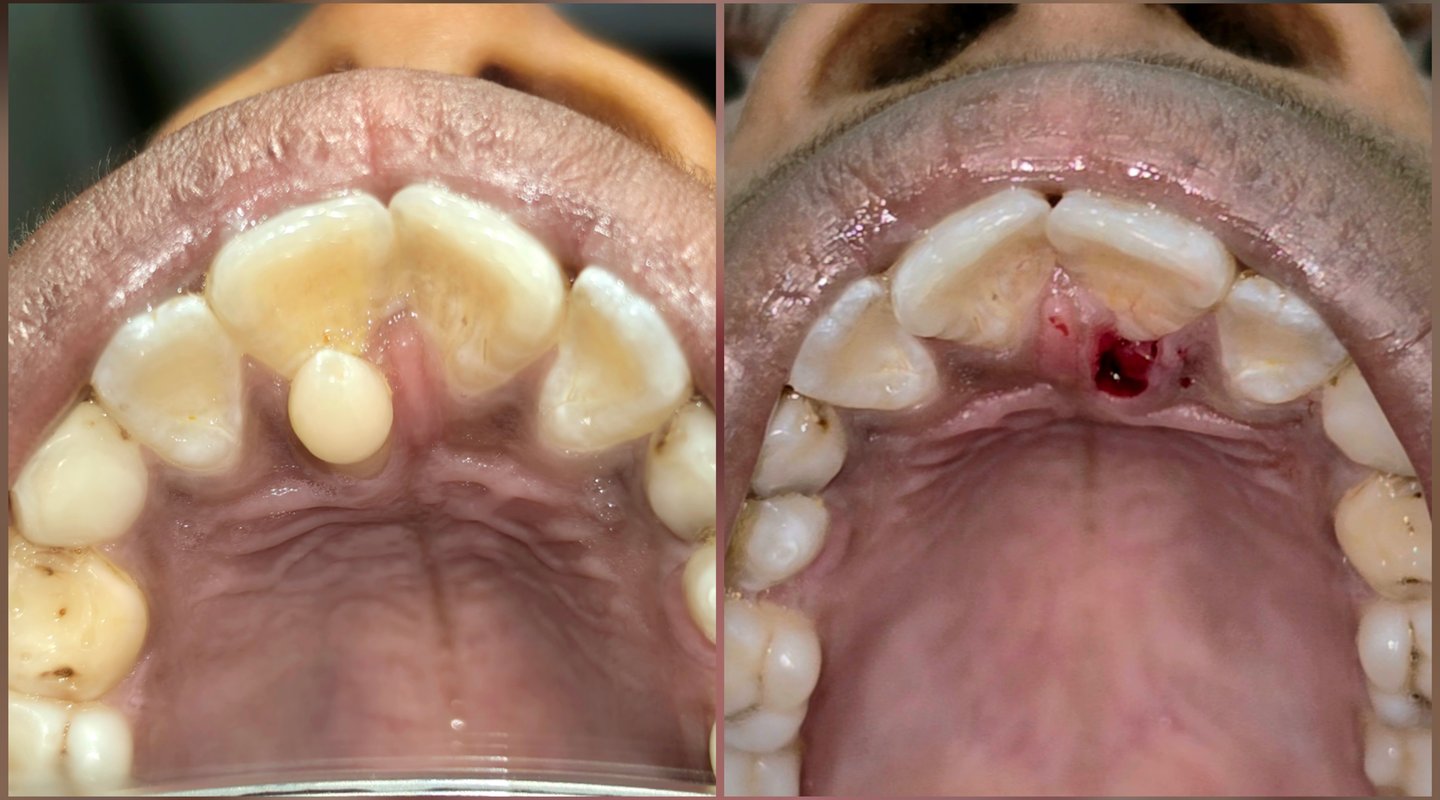

📸 Before & After Results (Conversion Booster)

Nothing builds trust like real results 💯

✔️ What You Can Expect:

Proper alignment of front teeth

Natural eruption after removal

Improved smile aesthetics

📸 We regularly share:

Pre-treatment condition photos

Post-treatment smile results

👉 Ask your dentist to show before–after cases before starting treatment.